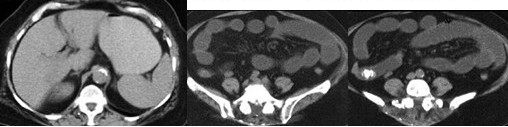

男,30岁,有胆结石病史,近日腹痛,腹胀,CT检查如图,应诊断为

A:胆石症

B:胆石性肠梗阻

C:肠结核

D:小肠克罗恩病

E:小肠淋巴瘤